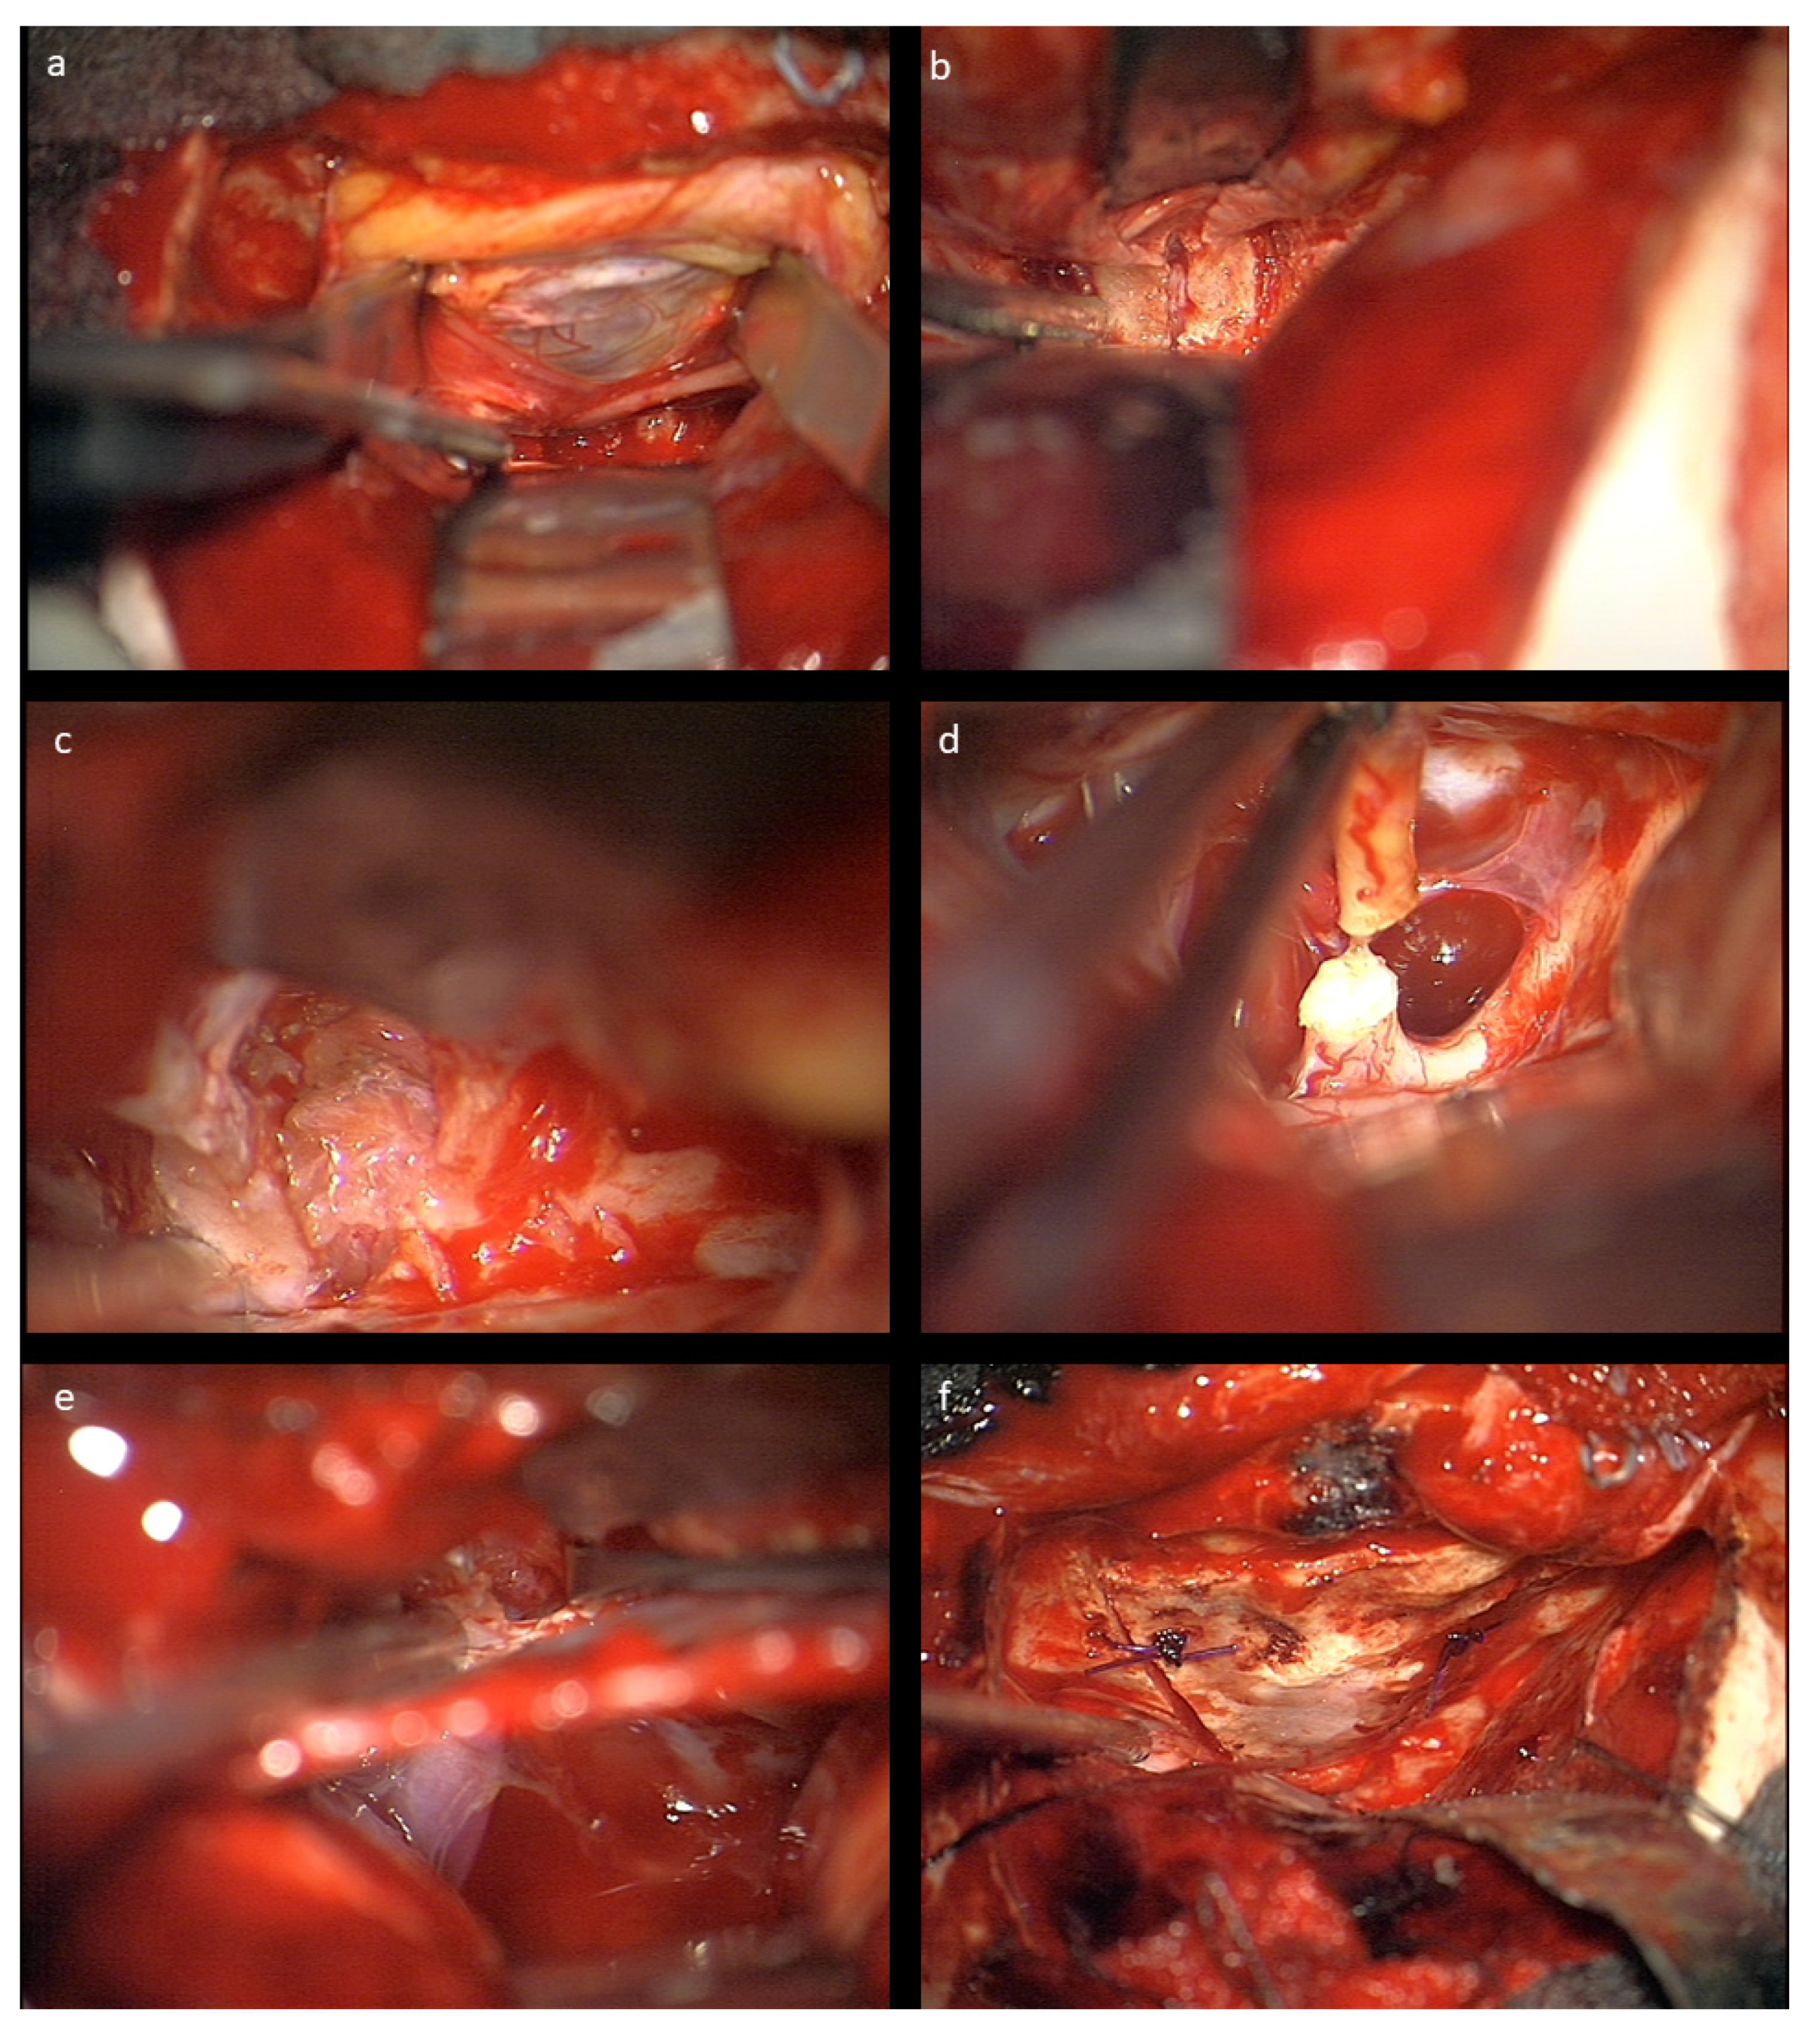

No intraoperative or immediate post-operative complications were observed, and patients were usually discharged with orbital swelling and not yet or returning levator palpebra function. In the follow-up, two children developed enophthalmos, one with minimal levels and one with moderate ptosis due to levator palpebra muscle weakness. Both children had received radiotherapy prior to surgery. The other eight (80%) children had no obvious oculomotor or cosmetic deficit of eye position and movement. Figure 4 shows an example of resolution of exophthalmos on MRI after tumor removal.

Figure 4. Exemplary MR imaging follow-up of a child with (a) preoperative exophthalmos on the left side and (b) postoperative normal eye position.